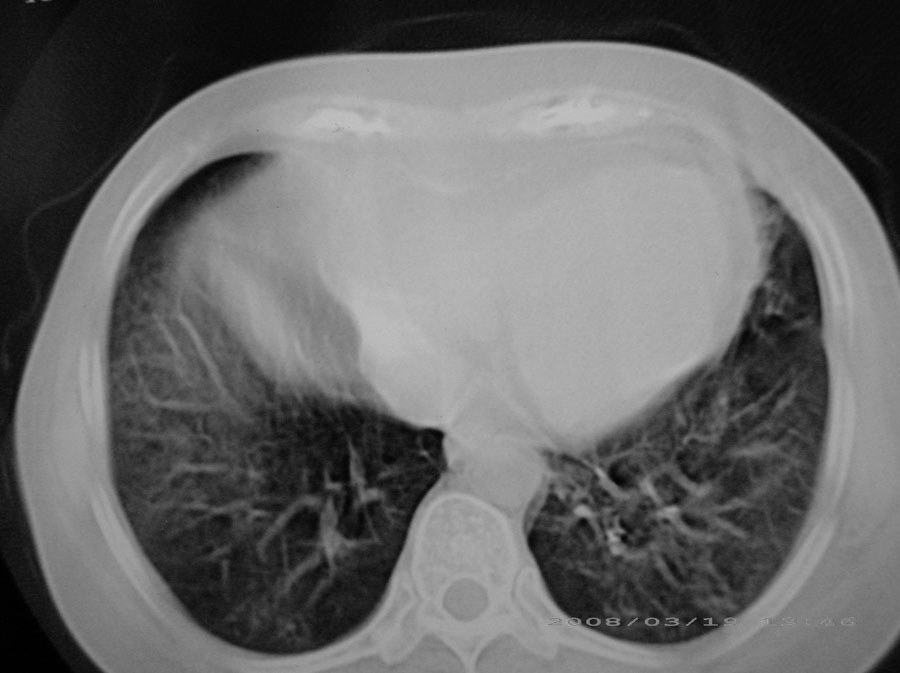

粟粒性结核

细支气管肺泡癌

本病例主要是癌性淋巴管炎与结节病的鉴别。好好查查吧。

密漫性沿纹理走行小结节影;有间质纤维化;可考虑尘肺;以图而论

血行播散性肺结核

两肺间质性病变!考虑间质纤维化?间质性肺炎!

双肺网状结构,小叶间质结节状增厚,考虑结节病

综合大家意见,结核、结节病、肺泡细胞癌均有可能,间质性肺炎暂不考虑,病灶纠集不明显,纵隔未见钙化淋巴结,尘肺可能性不大,但还是要密切结合临床诊断。

今天重新仔细看了看,矽肺确实不能除外,病灶主要表现为间质结节及纤维化。好好问问病史吧。